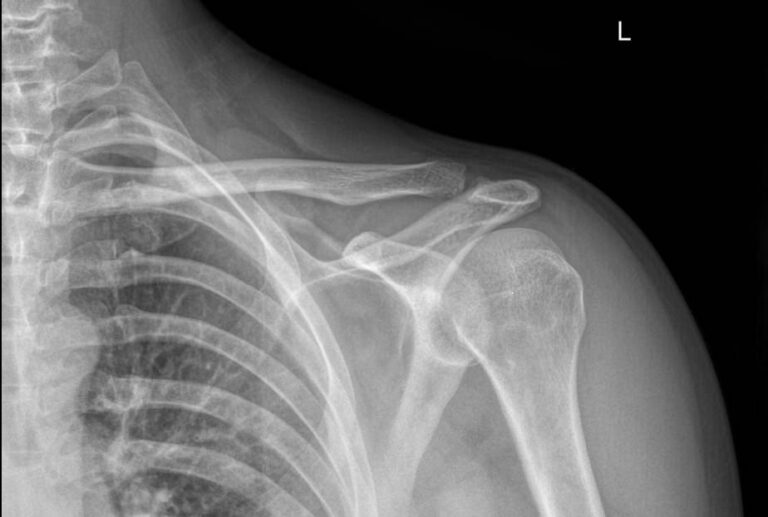

В случае травмы на снимке могут быть обнаружены:

• Отек мягких тканей;

• Расширение суставной щели;

• Ключица приподнята над акромионом;

• Перелом ключицы или клювовидного отростка лопатки;

• Изменения, свойственные дегенеративным процессам костной ткани.